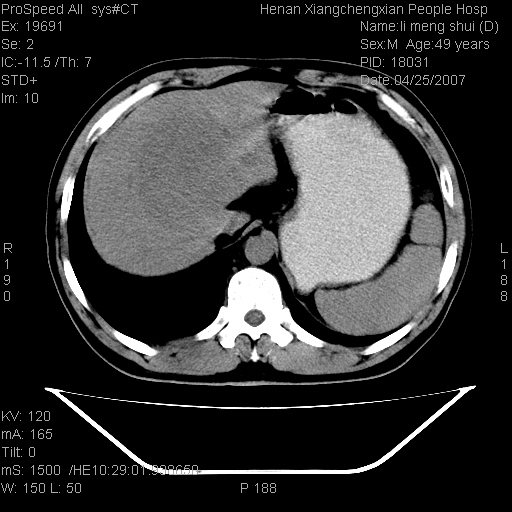

| 患者,男,49岁, 腹疼伴恶心\\呕吐20天,20天前无明显诱因出现右上腹部疼痛,钝疼,无放射,伴恶心\\呕吐,不伴发热.患者不愿增强. b超:肝脏右叶实性占位. ct:肝脏右叶可见一巨块状圆形低密度影,大小约93mm*84mm,其内可见点状高密度影,胆囊、胰腺、脾脏大小、形态及密度未见异常,腹膜后间隙未见肿大淋巴结影。 印象:肝脏右叶巨大肿块,性质待定,建议增强并穿刺活检进一步确诊。 ct平扫: ![]() ![]() ![]() ![]() ![]() ![]() ![]() ![]() ![]() ![]() ![]() ![]() ![]() ![]() ![]() ![]() ![]() 肝脏右叶肿块ct引导下穿刺活检术 患者于16时05分仰卧于ct检查台上,首先行肝脏ct扫描确定进针位置、深度、角度。在局麻下行ct引导下肝脏右叶肿块穿刺活检术。常规消毒、铺巾、局麻。在ct引导下使活检针经右侧腋中线、第9肋间隙垂直胸壁进针90mm,针头进入病变预定位置。在病变预定位置多点、多方向抽取小米样病变组织多块,涂片五张送病理检查。术后穿刺点局部无出血,未出现腹腔积液等并发症。术中及术后患者生命体征稳定,手术于17时10分成功完成。患者安返病房。 穿刺片 ![]() ![]() ![]() ![]() ![]() ![]() ![]() ![]() ![]() ![]() ![]() ![]() ![]() ![]() ![]() ![]() 病理结果肝细胞癌 ![]() 原贴地址:http://www.radinet.com.cn/forum_view.asp?forum_id=4&view_id=24130 ok |